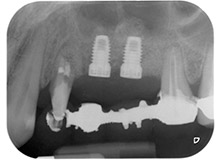

lesión periodontal apical en la pieza dental 24

Fig. 1: En una paciente de 58 años, la radiografía previa a la intervención mostraba una lesión periodontal apical en la pieza dental 24, así como una pérdida horizontal de hueso alveolar en el segundo cuadrante.

Mujer de 58 años de edad, que además es una apreciada colega y amiga, y se quejaba de dolor y de un aumento en la movilidad del pilar del puente de la pieza dental 24. También había inflamación periodontal, con bolsas de una profundidad de 7 mm en sentido mesiobucal y más de 12 mm en sentido distal, así como furcación de tercer grado. Asimismo, la radiografía reveló una lesión periodontal extensa alrededor de la región apical de la pieza dental 24 (figura 1) tratada previamente con endodoncia (alio loco).

Un año antes, las piezas dentales 25 y 26 se habían extraído por razones traumáticas y endo-periodontales antes de la colocación del puente. Se diagnosticó una lesión endo-periodontal combinada en la pieza dental 24, pero su componente etiológico principal no estaba claro. La paciente declaró su voluntad de mantener el pilar del puente de las piezas 24 y 27 y afirmó que no aceptaría una prótesis extraíble final, ni siquiera provisional. Por lo tanto, se acordó intentar por todos los medios conservar ambos dientes, a pesar del mal pronóstico que mostraban las pruebas radiológicas y clínicas.

Por último, después de una incisión perióstica, el sitio se suturó de forma pasiva con un colgajo avanzado frontal, utilizando material de sutura absorbible 5-0 (figura 15). La radiografía posoperatoria muestra ambos implantes en sus posiciones verticales correctas (figura 16).

radiografía posoperatoria

Fig. 16: La radiografía posoperatoria muestra ambos implantes en sus posiciones correctas, con material sustituto óseo alrededor de los ápices procedente de la elevación interna del seno. También hay material visible alrededor de las raíces de la pieza 24 procedente del procedimiento de GTR.